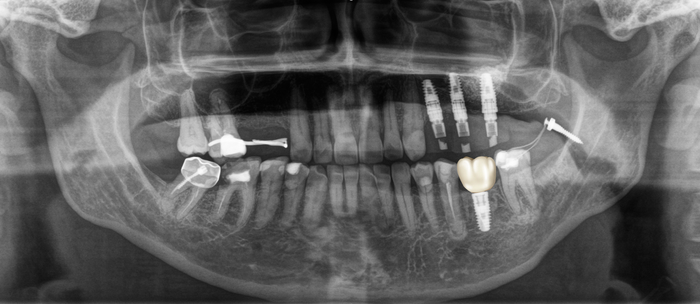

Ниже панорамный снимок, где хорошо видно, как из-за длительного (овер 10 лет) отсутствия 6-го зуба на нижней челюсти слева (на снимке справа) соседние зубы – седьмой и восьмой – наклонились в сторону отсутствующего.

(На верхней челюсти с этой же стороны были удалены четвертый, шестой и седьмой зубы. На их месте установлены имплантаты и проведен синус-лифтинг. Пятого зуба у пациентки не было.

Если посмотреть внимательно, то можно обратить внимание на то, что седьмой и восьмой зубы стоят в зубном ряду выше, чем с противоположной стороны:

Этот снимок был сделан после операции. Если приглядеться, то можно увидеть область, откуда был взят костный блок, и его очертания в месте его фиксации винтиками:

Вот результат после установки временной коронки и удаления минивинта:

Временные коронки делаются из фрезерованной пластмассы, поэтому не рентгеноконтрастны, хотя, если посмотреть внимательно, то можно увидеть неявные очертания коронок.